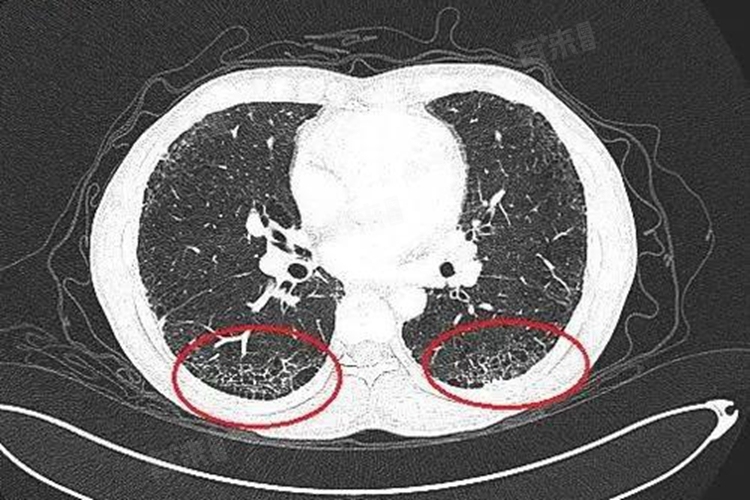

3、支气管扩张:支气管扩张是一种常见的呼吸系统疾病,由于支气管壁结构受到破坏,导致支气管异常扩张。在影像学检查中,支气管扩张可能表现为支气管壁的增厚和管腔的扩张,部分情况下可能伴随有肺部的纤维条索影,可能提示支气管炎症的进一步加重。

4、肺纤维化:肺纤维化是一种慢性肺部疾病,特征是肺部组织逐渐被纤维性组织所替代,导致肺组织变得硬化和失去弹性,最终影响呼吸功能。在肺纤维化的过程中,受损的肺组织会被纤维组织所修复,在影像学检查中表现为索条影,其严重程度相对较高。

5、恶性病变:纤维条索影的出现也可能与恶性病变有关,当条索影边界不清、边缘模糊,伴有实变时,需高度警惕恶性病变的可能性,条索影的严重程度极高。